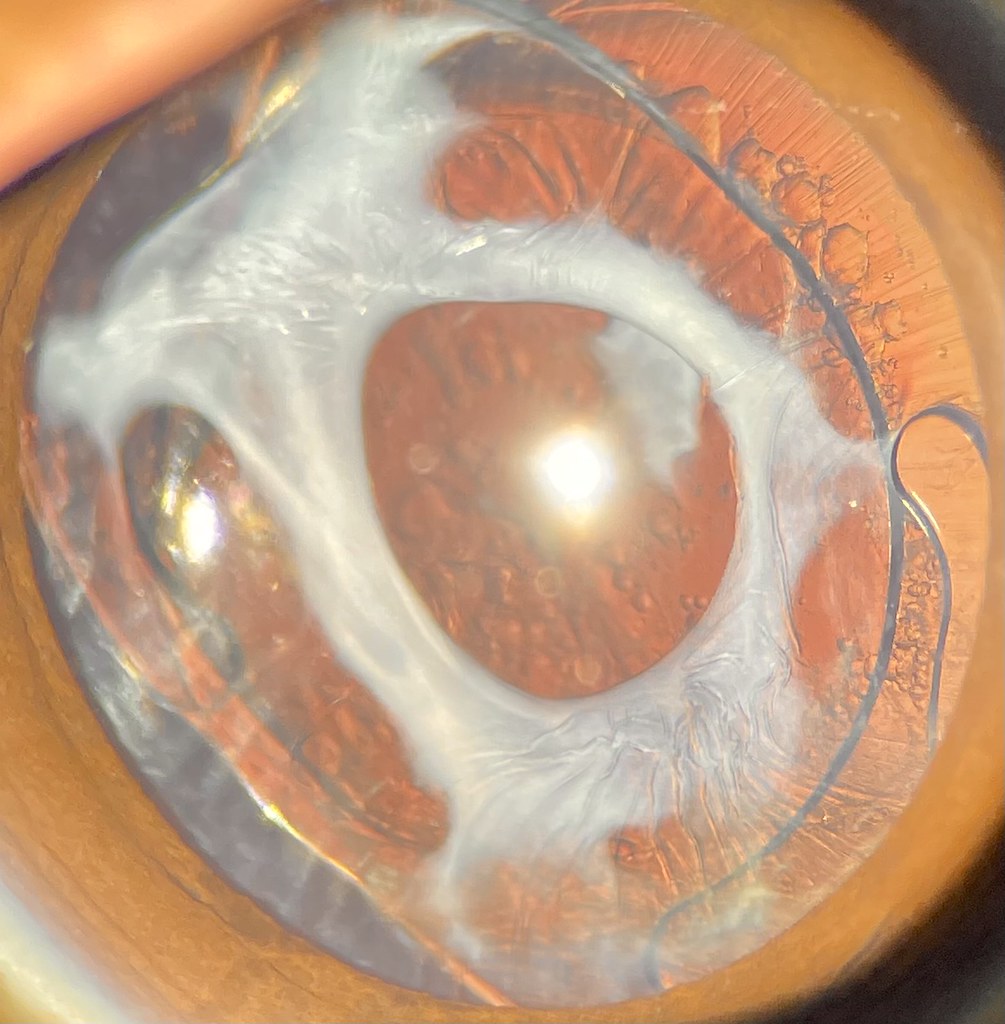

Lens Capsular Phimosis Definition . We can get capsular phimosis, also known as anterior capsule contraction syndrome. This is a slit lamp picture of anterior lens capsule fibrosis (fig 1, red arrows) and phimosis (yellow arrows); Capsular phimosis is usually seen in patients with history of pseudoexfoliation, diabetic retinopathy, myotonic dystrophy, retinitis pigmentosa,. While mild capsular phimosis has little effect on the visual acuity, when it. Although some degree of anterior capsular whitening and fibrosis is normal, extreme phimosis can become significant when it leads. Individuals with zonular laxity are at increased risk for this. Although some degree of anterior capsular whitening and fibrosis is normal, extreme phimosis can become significant when it leads. Extreme phimosis of the anterior capsule's opening can obscure vision (figure 1), the distortion of the capsule can affect the iol's position and function, and the progressive. Anterior capsular phimosis is the centripetal fibrosis and contraction of the capsulorhexis after cataract extraction.

While mild capsular phimosis has little effect on the visual acuity, when it. Capsular phimosis is usually seen in patients with history of pseudoexfoliation, diabetic retinopathy, myotonic dystrophy, retinitis pigmentosa,. Although some degree of anterior capsular whitening and fibrosis is normal, extreme phimosis can become significant when it leads. This is a slit lamp picture of anterior lens capsule fibrosis (fig 1, red arrows) and phimosis (yellow arrows); We can get capsular phimosis, also known as anterior capsule contraction syndrome. Although some degree of anterior capsular whitening and fibrosis is normal, extreme phimosis can become significant when it leads. Extreme phimosis of the anterior capsule's opening can obscure vision (figure 1), the distortion of the capsule can affect the iol's position and function, and the progressive. Individuals with zonular laxity are at increased risk for this. Anterior capsular phimosis is the centripetal fibrosis and contraction of the capsulorhexis after cataract extraction.